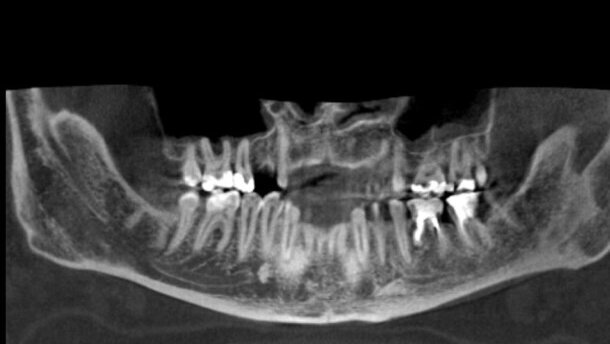

Dwudzielny kanał żuchwy jest anatomiczną odmianą budowy kanału żuchwy oznaczającą, że kanał żuchwy jest podzielony na dwie gałęzie. W zależności od techniki badania występuje on u 0,08%-65% ludzi, najlepiej widoczny jest w badaniu CBCT. Obecność dwudzielnych kanałów może powodować nieprzewidziane powikłania podczas ekstrakcji zębów lub osteotomii żuchwy, być przyczyną niepowodzenia w znieczulaniu dolnych zębów trzonowych i przedtrzonowych, warunkować leczenie i planowanie implantologiczne, powodować dolegliwości bólowe podczas użytkowania protez ruchomych.

Występowanie dwudzielnych kanałów żuchwy wielokrotnie badano z wykorzystaniem różnych technik. Otrzymane wyniki istotnie różnią się w zależności od tego, czy występowanie kanału oceniano na zdjęciach pantomograficznych (OPT – orthopantomography), tomografii komputerowej (CT – Computed Tompography) czy tomografii komputerowej wiązką stożkową (CBCT – Cone Beam Computed Tompography), (Tab.1).

Na podstawie zdjęć pantomograficznych obecność kanału stwierdzano u 0,08%-8,3% pacjentów.1,3-7 W tomografii komputerowej wykryto dwudzielny kanał u 30,6%-41% pacjentów.8-10 Dwudzielny kanał żuchwy najczęściej obserwowano w badaniu CBCT – u 10,2%-65% badanych.11-17 Z powodu istotnej różnicy w skuteczności wymienionych metod zaleca się analizowanie występowania dodatkowego kanału żuchwy w oparciu o badania CBCT.12,17-19

Muinelo-Lorenzo i wsp. (9) stwierdzili, że zaledwie 37,8% dwudzielnych kanałów żuchwy wykrytych w badaniu CBCT jest widocznych na zdjęciach pantomograficznych. Natomiast Naithon i wsp.17 porównywali skuteczność i użyteczność wielorzędowej tomografii komputerowej (MSCT) względem tomografii wiązką stożkową (CBCT). Wyniki ich badań wskazują, że ponad 20% dodatkowych kanałów żuchwy zaobserwowanych w badaniu CBCT nie jest widocznych na badaniu MSCT. Zatem diagnostyka CBCT wydaję się najlepszą pośród dostępnych.